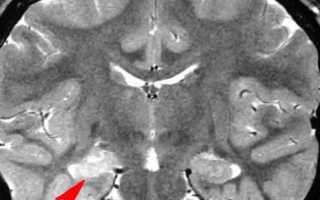

в мозговой ткани животных после судорог, вызванных различными факторами (инъекциями амидопирина, электрошок, аудигенная стимуляция и др.), установлено значительное повышение активности холниэстеразы. Высказывается мнение, что основную роль в механизме повышения эпилептической возбудимости играет нарушение соотношения между катехоламинами и ацетилхолином. Это согласуется с данными о создании каиновой модели экспериментальной ВЭ, при которой в гиппокампе возникают патоморфологические изменения, сходные с таковыми при ВЭ человека. Канновая кислота вызывает значительное увеличение содержания АХ и уменьшение содержания норадреналнна. Одновременно понижается активность, глутаматкарбокснлазы и уменьшается обратный захват глутами новой кислоты, что сопровождается возрастанием активности нейромедиатора возбуждения глутамата и ослаблением ГАМКер-гической передачи с возникновением эпилептических судорог.